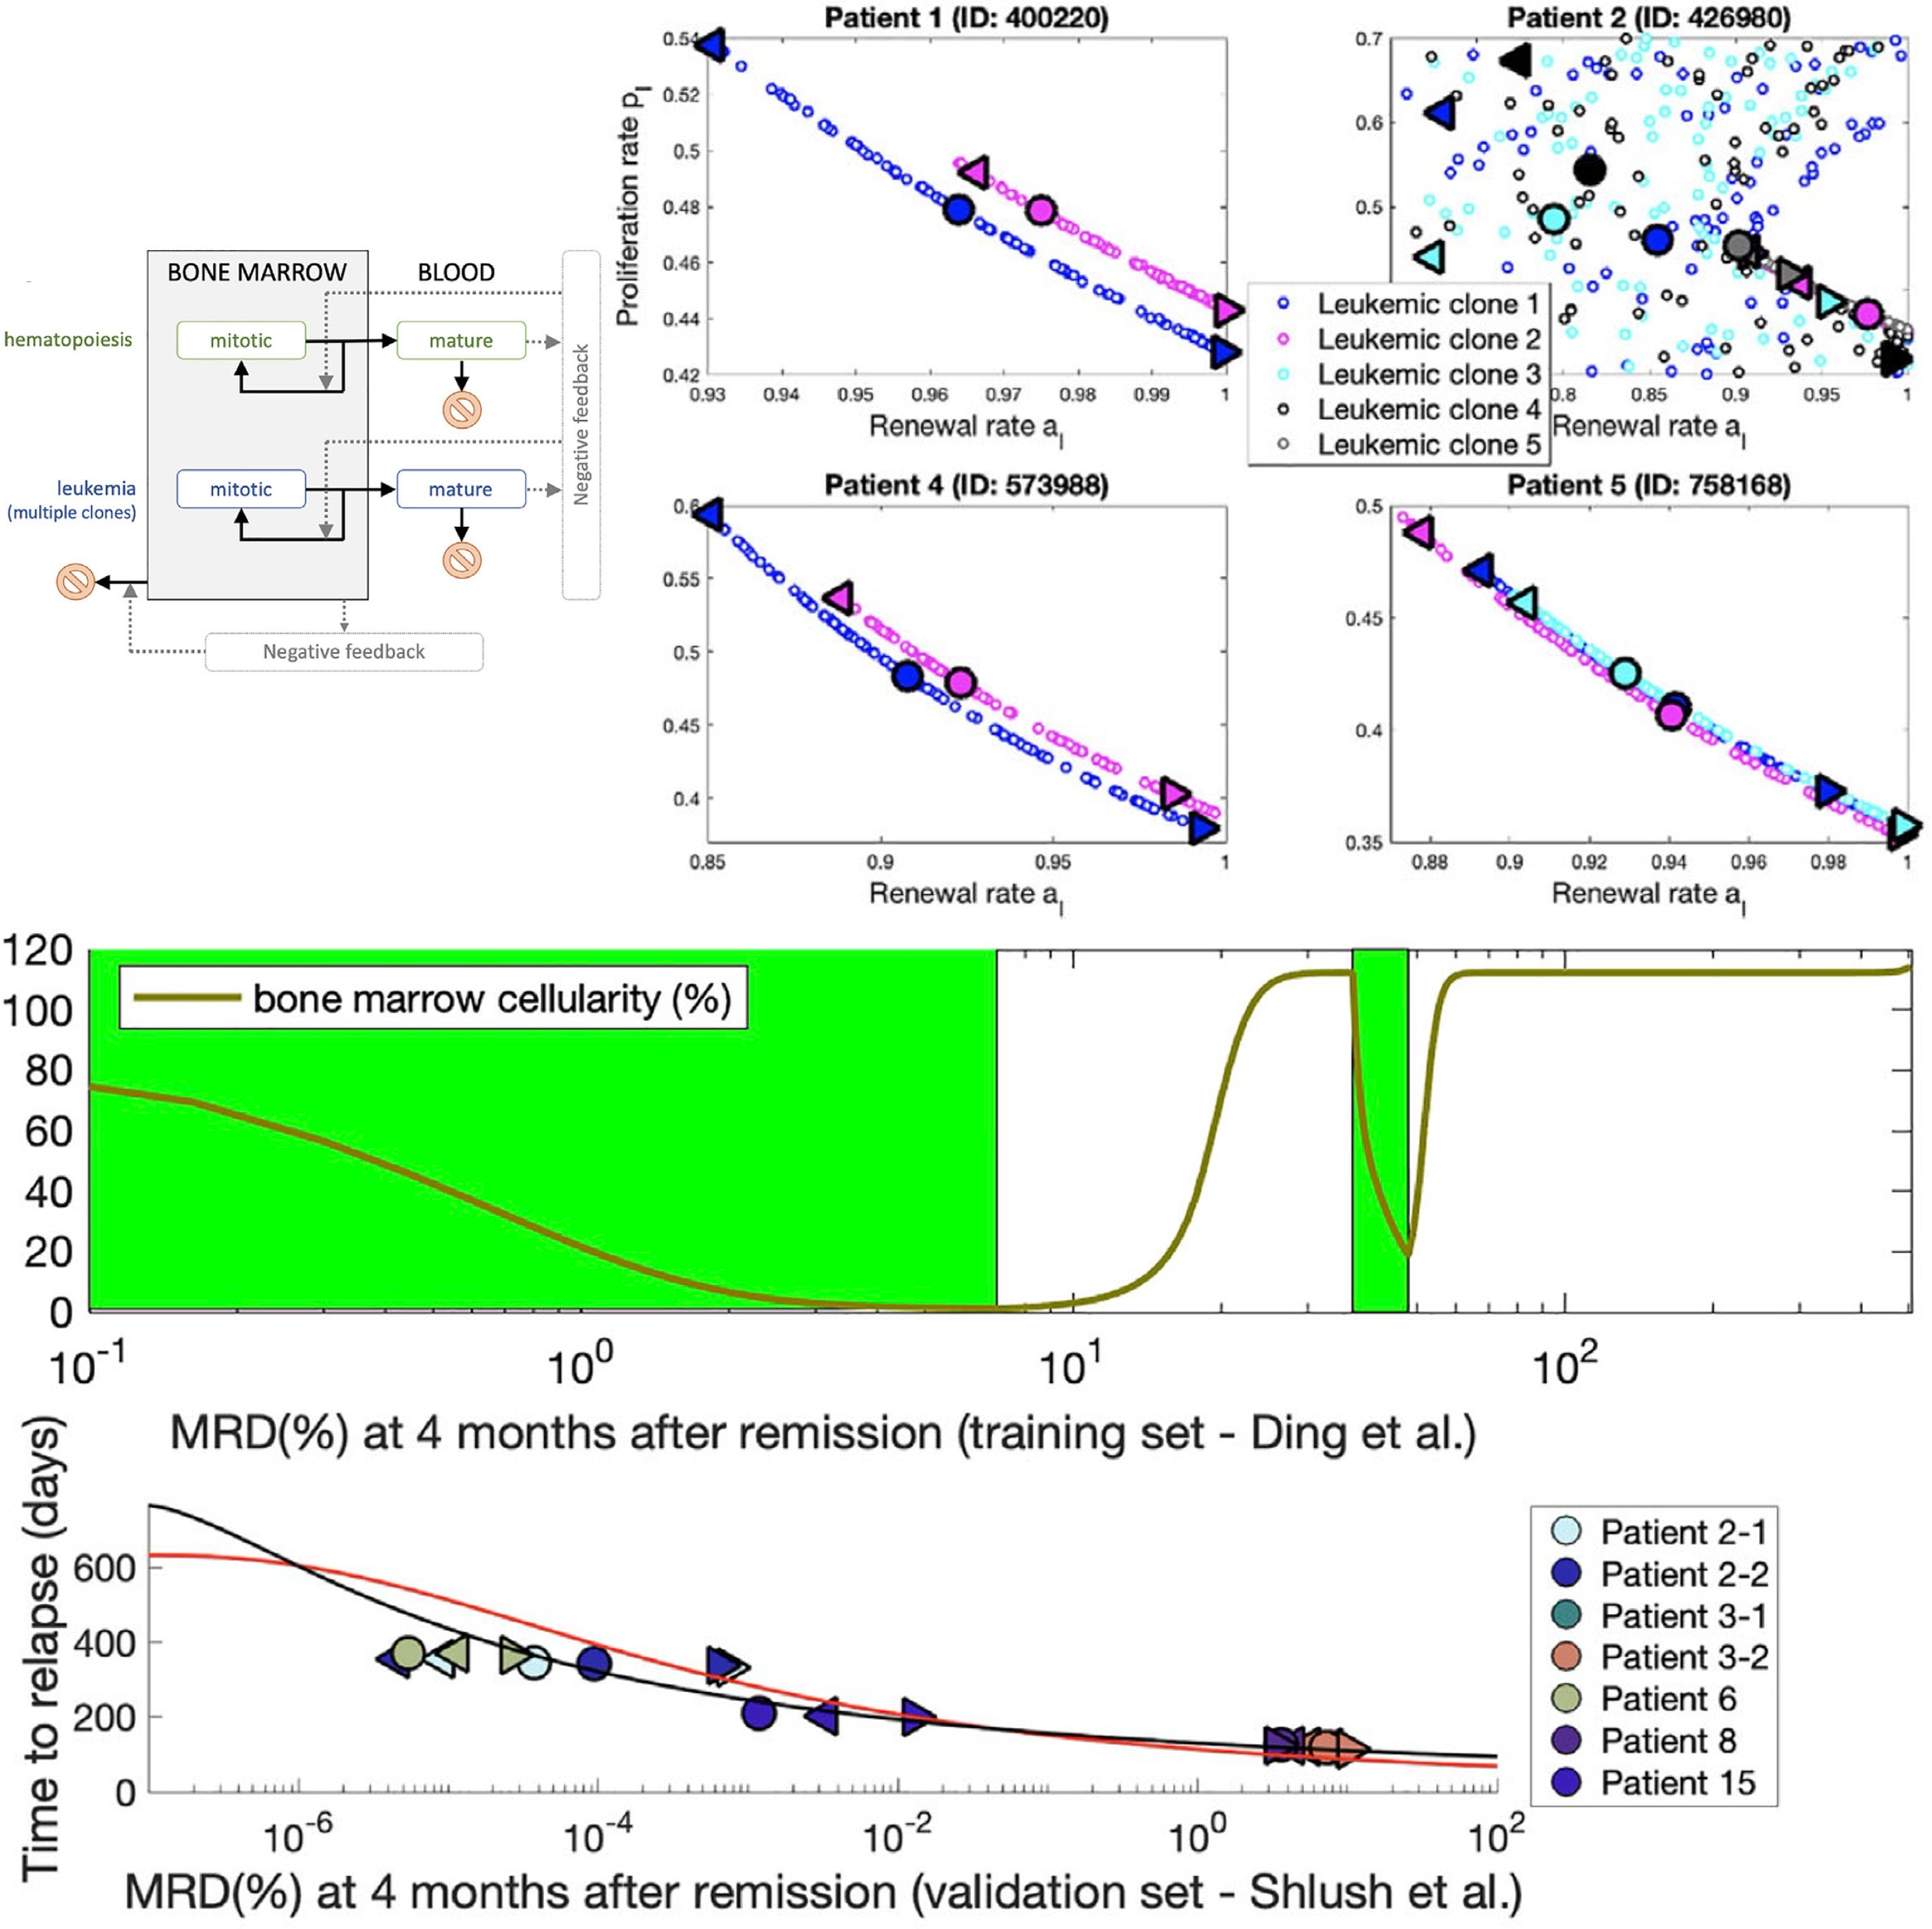

Predicting time to relapse in acute myeloid leukemia through stochastic modeling of minimal residual disease based on clonality dataComputational and systems oncology, 2021

Predicting time to relapse in acute myeloid leukemia through stochastic modeling of minimal residual disease based on clonality dataComputational and systems oncology, 2021Event-free and overall survival remain poor for patients with acute myeloid leukemia. Chemoresistant clones contributing to relapse arise from minimal residual disease (MRD) or newly acquired mutations. However, the dynamics of clones comprising MRD is poorly understood. We developed a predictive stochastic model, based on a multitype age-dependent Markov branching process, to describe how random events in MRD contribute to the heterogeneity in treatment response. We employed training and validation sets of patients who underwent whole-genome sequencing and for whom mutant clone frequencies at diagnosis and relapse were available. The disease evolution and treatment outcome are subject to stochastic fluctuations. Estimates of malignant clone growth rates, obtained by model fitting, are consistent with published data. Using the estimates from the training set, we developed a function linking MRD and time of relapse with MRD inferred from the model fits to clone frequencies and other data. An independent validation set confirmed our model. In a third dataset, we fitted the model to data at diagnosis and remission and predicted the time to relapse. As a conclusion, given bone marrow genome at diagnosis and MRD at or past remission, the model can predict time to relapse and help guide treatment decisions to mitigate relapse.